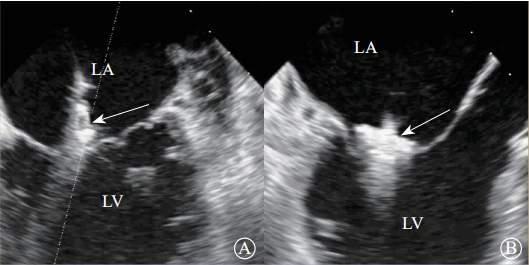

超声心动图在MR介入术中起着不可或缺的作用,下面以目前最为成熟的经导管二尖瓣夹合术MitralClip为例,阐述MR介入术中的超声评价。MitralClip是在经食管超声心动图实时监测和引导下的操作,所有的导管操作由经食管超声心动图监测和引导[17]。经食超声心动图首先引导房间隔穿刺,使得房间隔穿刺点距二尖瓣瓣环平面的高度为3.5~4.0 cm(图12)。之后,经食管超声心动图引导输送系统进入左心房并调弯、顶端垂直指向二尖瓣口。接着,经食管超声心动图引导夹合器在二尖瓣上方定位、夹合器进入左心室、引导夹合器捕获和夹合瓣膜。夹合器捕获瓣膜位置,应该位于彩色多普勒显示反流束最大处。在整个手术过程中,两个超声视野非常重要,为手术的工作切面,其中X-plane双切面,包括三腔心切面(左心室长轴切面)及二尖瓣交界处二腔心切面(图13)。三腔心切面可以显示二尖瓣A2、P2的位置,捕获瓣膜前二尖瓣夹合器应该在这个切面显示为V字形,此时瓣夹合器臂与二尖瓣开放线垂直,分别位于A2、P2的位置,在该切面通过调整夹合器位置可使得夹合器更靠近前叶或后叶;二尖瓣交界处二腔心切面显示P1、A2、P3,捕获瓣膜前二尖瓣夹合器在该平面应该为直线形,在该切面通过调整夹合器位置可使得夹合器更靠近瓣环内交界(P3或A3)或外交界(P1或A1)。另外一个工作切面为三维超声心动图的“二尖瓣外科视野”,可以整体观察夹合器的位置、臂指向的方向(图14)。目前有限经验显示,经心尖二尖瓣夹合术(ValveClamp)术中超声心动图指导和MitralClip总体上类似,但仍有部分差异,其超声心动图规范尚在探索中。

注:LA,左心房;LV,左心室

图13 经食管X-plane双切面显示夹合器与二尖瓣前后叶垂直(箭头所示)A. 二尖瓣交界处二腔心切面,显示夹合器为直线形;B. 左心室长轴切面,显示夹合器为“V”字形